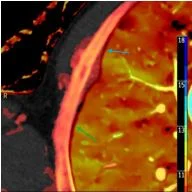

Z-effective map: See the pleura so well!